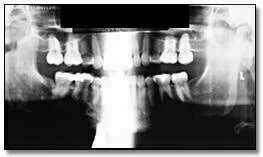

Ví dụ về hình ảnh toàn cảnh thiếu sáng

Hình ảnh với liều tia không đủ có thể dẫn đến không phát hiện được các đặc điểm bệnh lý. Hình 35a là một phiên bản nâng cao kỹ thuật số. Chúng ta có thể dễ dàng thấy chiếc răng hàm thứ ba bên phải bị tác động mà bị mờ đi trên bản gốc. Sự tăng cường này cũng chứng tỏ rõ ràng bệnh nhân có một bệnh lý liên quan đến răng hàm dưới thứ hai bên phải.